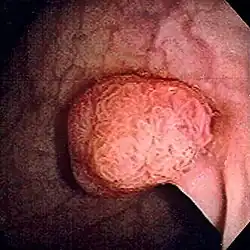

| Polyp of sigmoid colon as revealed by colonoscopy. Approximately 1 cm in diameter. The polyp was removed by snare cautery. | |

Polyps are either pedunculated (attached to the intestinal wall by a stalk) or sessile (grow directly from the wall).[5][6]: 1342 In addition to the gross appearance categorization, they are further divided by their histologic appearance as tubular adenoma which are tubular glands, villous adenoma which are long finger like projections on the surface, and tubulovillous adenoma which has features of both.[6]: 1342